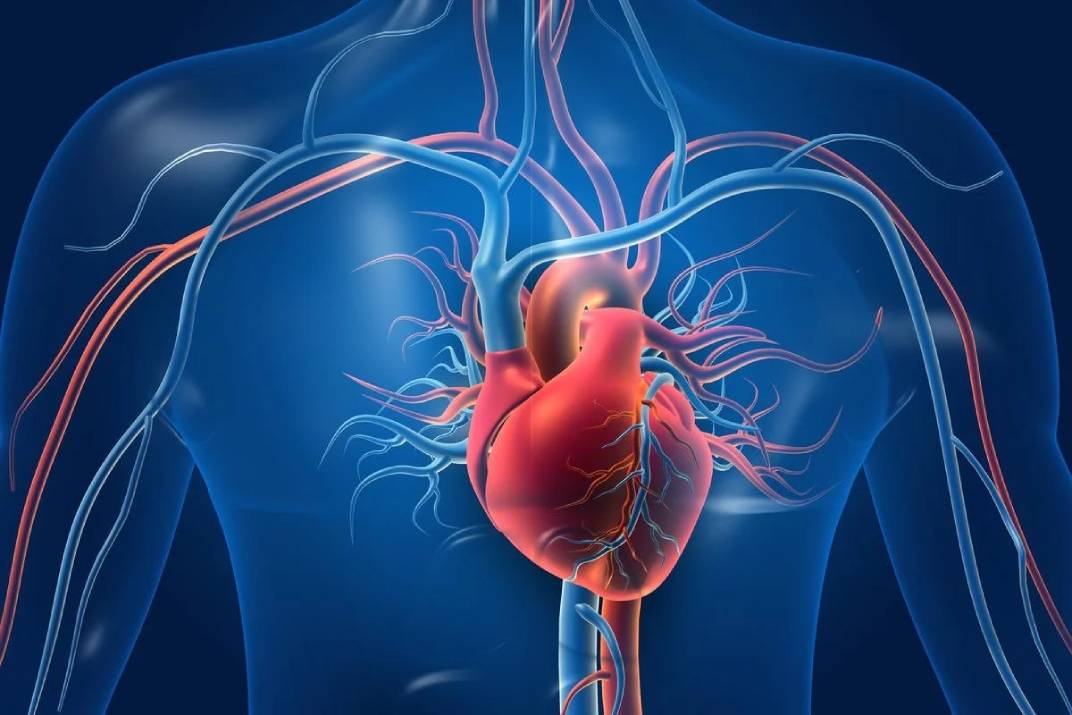

صحة و جمالحذر استشاري أمراض القلب وقسطرة الشرايين، الدكتور خالد النمر،مرضى القلب من أي ضغوط خلال مناسك…